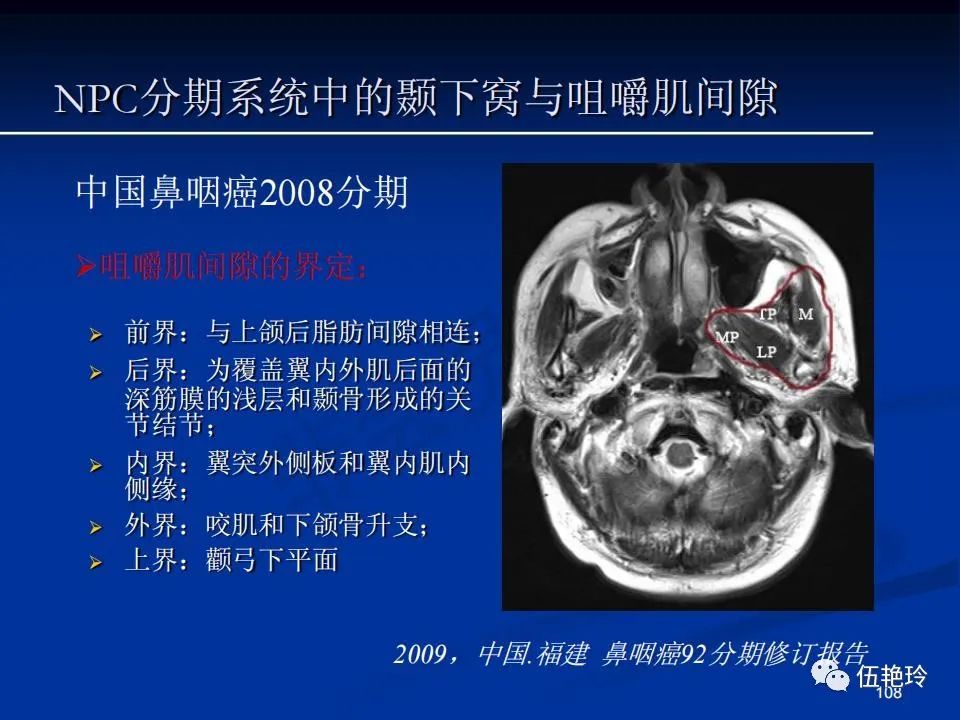

颞下窝与咀嚼肌间隙

2.31 向上颅内:①鼻咽顶壁→破裂孔(岩尖、斜坡)→蝶窦、海绵窦;②鼻咽顶壁→蝶骨基底部→蝶窦、海绵窦;③鼻咽侧壁→茎突前间隙→蝶骨大翼(卵圆孔)→海绵窦;④鼻咽侧壁→茎突前间隙→翼腭窝→ 颞下窝;⑤鼻咽前壁→鼻腔→翼突、翼腭窝→眶下裂→眶尖→海绵窦;⑥鼻咽前壁→鼻腔→上颌窦、筛窦;